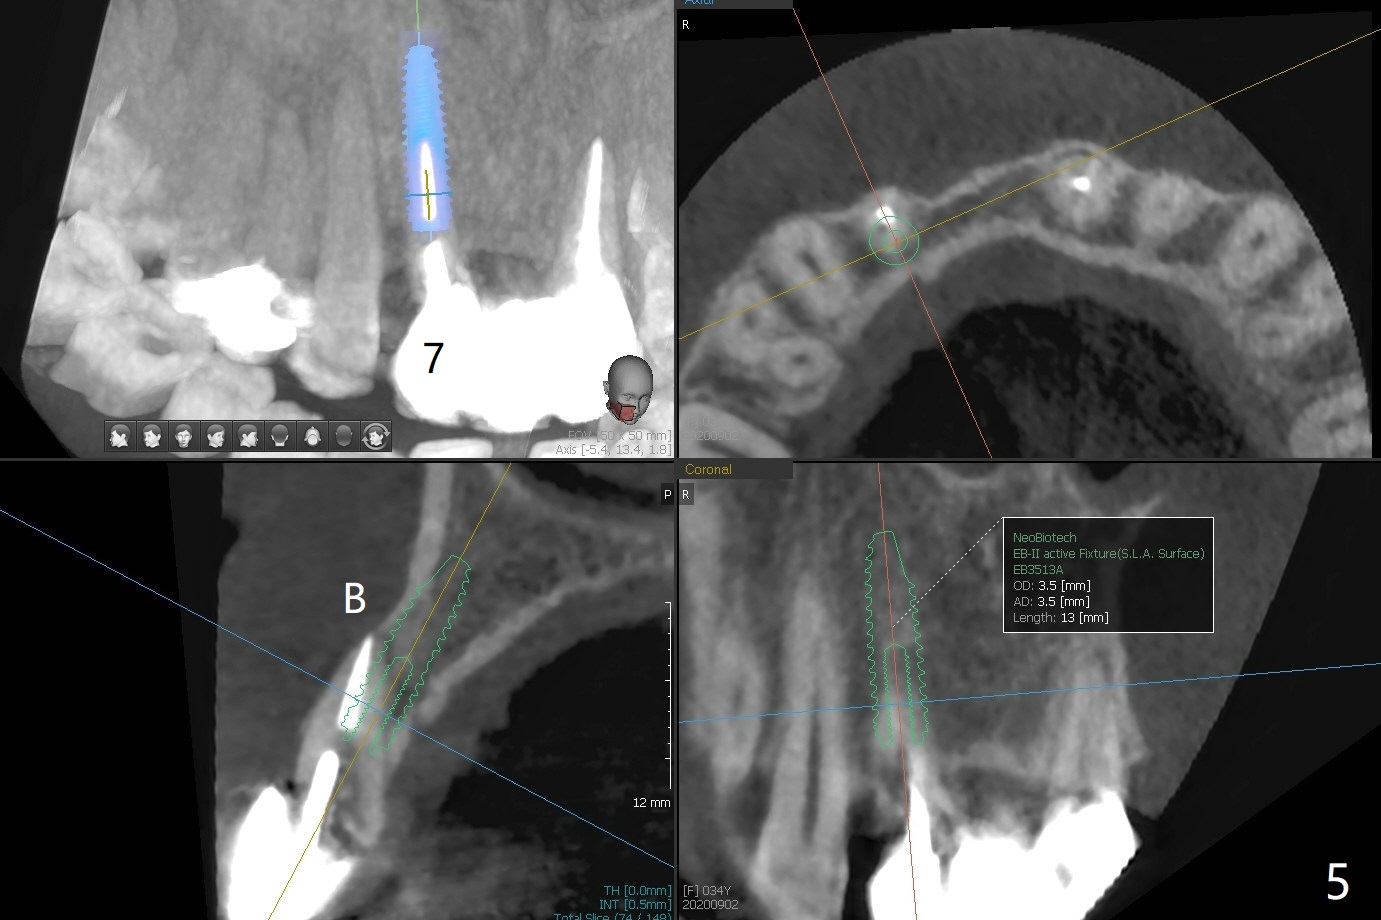

A 34-year-old woman requests fixing the failed anterior FPD (Fig.1). The edentulous alveolus looks thin; 1-piece implant may be indicated at most. A regular narrow 2-piece implant will be placed at the lateral incisor (Fig.2). CT is necessary for treatment planning. Impression has been taken for stent fabrication. 34岁女,一年半前来诊所(图一,二(侧切牙种植,做悬臂桥,暂时保留左上1牙冠)),希望修复右上门牙桥。现在终于要求立即做,基牙处牙龈红肿 (图三(今天做深洗)),牙桥颊侧移位(图四),侧切牙(7号牙)牙槽嵴也不是很宽,植入3.5毫米植体(两段式, IBS)还勉强(图五)。为了简化,避免悬臂桥,我还想在中切牙(8号牙)无牙处植入一段式2.5毫米植体(图六),适当做些牙槽嵴劈开(图六右上图:红线; from IBS cassette)。这周末徒手植入,她离开时应该有固定临时修复物。

一段式植体似乎不美观,其实它适用于近中远中空间狭窄地方,如这个病例,而两段式植体显得太粗,没有空间形成牙龈乳头,况且容易以后导致植牙周围炎。即刻临时牙冠手术第一天就起到美观作用,术后三四个月中反复调整,为永久性牙冠奠定基础。以下手术步骤就是为了这个目的。在中切牙之间切断牙桥,为右上1狭窄牙槽嵴拍摄照片(颊侧,咬合面观),切口,铬羊肠缝线牵拉,外科车针去除尖端牙槽嵴直到后者宽度达到~ 3毫米,使用1.2毫米一段式钻头,8 毫米,插入一个已经折断同样大小车针作为定位;拔除侧切牙,拍摄各式各样刮匙和肉芽组织去除器械,用1.6毫米钻头在腭侧骨板钻洞,深度9毫米,拍摄术中第一张根尖片;在中切牙处使用片状骨凿稍做骨扩张,必要时旋转式扩大器,之后完成牙槽嵴下植体放置,侧切牙牙槽窝以及中切牙术野插入无絮棉布,做必要基台制备,使用成品临时牙冠制作两个分开牙冠,确保牙龈下边缘,取出棉布,植骨,放置PRF膜,插入临时牙冠,尤其是中切牙牙冠和骨粉将改善颊侧,腭侧(与图四箭头对比)饱满度,最后缝合,调整咬合。7,8号牙骨质密度分别为700和 500单位(图七,八)。